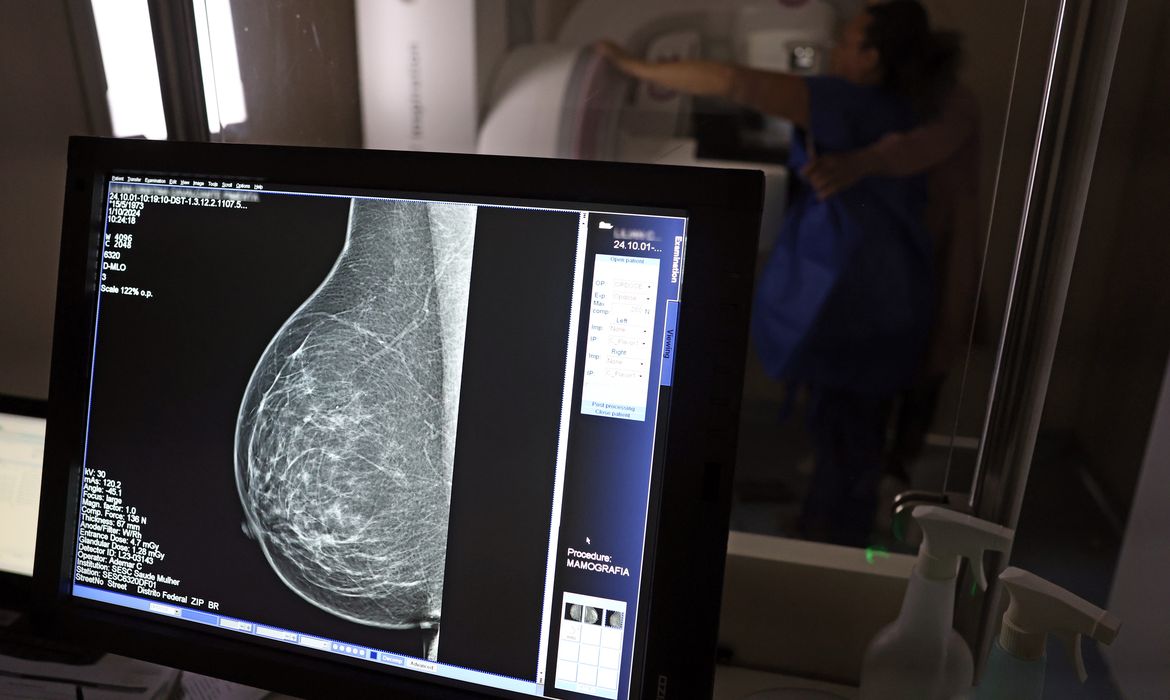

Falta de acesso a mamógrafos limita prevenção do câncer de mama

Relatório mostra disparidades regionais e baixa cobertura no Brasil

No mês de conscientização sobre o câncer de mama, um relatório destaca a importância de acesso igualitário ao rastreamento e tratamento da doença. Segundo o Atlas da Radiologia no Brasil, do Colégio Brasileiro de Radiologia e Diagnóstico por Imagem (CBR), o acesso aos mamógrafos ainda é um desafio.

O país tem 6.826 equipamentos registrados, sendo 96% em funcionamento. Metade deles está disponível no Sistema Único de Saúde (SUS), responsável por atender 75% da população. Isso equivale a 2,13 mamógrafos por 100 mil habitantes dependentes do SUS.

Na saúde suplementar, que cobre 25% da população, o cenário é mais favorável: 6,54 aparelhos por 100 mil beneficiárias, quase o triplo da rede pública. O Acre exemplifica essa disparidade — são 35,38 mamógrafos por 100 mil habitantes na rede privada, contra 0,84 no SUS.

Há disparidades regionais. Roraima tem a menor proporção (1,53 por 100 mil), seguida do Ceará (2,23) e Pará (2,25). A Paraíba lidera o ranking (4,32), à frente do Distrito Federal (4,26) e do Rio de Janeiro (3,93).

Segundo a coordenadora da Comissão Nacional de Mamografia do CBR, Ivie Braga de Paula, todos os estados têm número suficiente de aparelhos para o exame. Mas um conjunto de gargalos dificultam o acesso e geram subutilização.

“Há problemas de informação, de comunicação, de acesso e logística, principalmente na Região Norte. Por exemplo, os mamógrafos ficam nas cidades mais centrais e a população ribeirinha não consegue chegar. Às vezes, tem que andar seis a sete horas de barco para fazer uma mamografia. Até nos grandes centros, as pacientes da periferia não têm informação suficiente e enfrentamdificuldades para marcar e chegar em um local com mamógrafo”, diz Ivie.

O Brasil tem uma cobertura muito baixa de mamografias: 24%. O ideal recomendado pela Organização Mundial da Saúde é de 70%. Mesmo em lugares como o estado de São Paulo, que tem a maior concentração de mamógrafos do país, a taxa gira em torno de 26%.

Em setembro, o Ministério da Saúde ampliou as diretrizes de rastreamento, recomendando que mulheres entre 40 e 49 anos realizem mamografias, mesmo sem sintomas. De acordo com o Instituto Nacional do Câncer (Imca), mais de 73 mil mulheres recebem o diagnóstico de câncer de mama anualmente no Brasil.

“O que é efetivo na redução da mortalidade é você descobrir o tumor antes de ter sintoma clínico. Quanto menor o tumor, melhor para a gente descobrir o tratamento e maior a chance de cura. E a gente só consegue fazer isso com exames de imagem", diz Ivie.

Ela explica que no caso de diagnóstico de um câncer de mama com menos de 1 cm, a chance de cura é de 95% em cinco anos, independentemente se ele é do tipo mais agressivo. "E esses tumores só vão ser detectados na mamografia. Essas pessoas que têm que ir fazer mamografia são mulheres saudáveis. Não são mulheres doentes”, acrescenta.